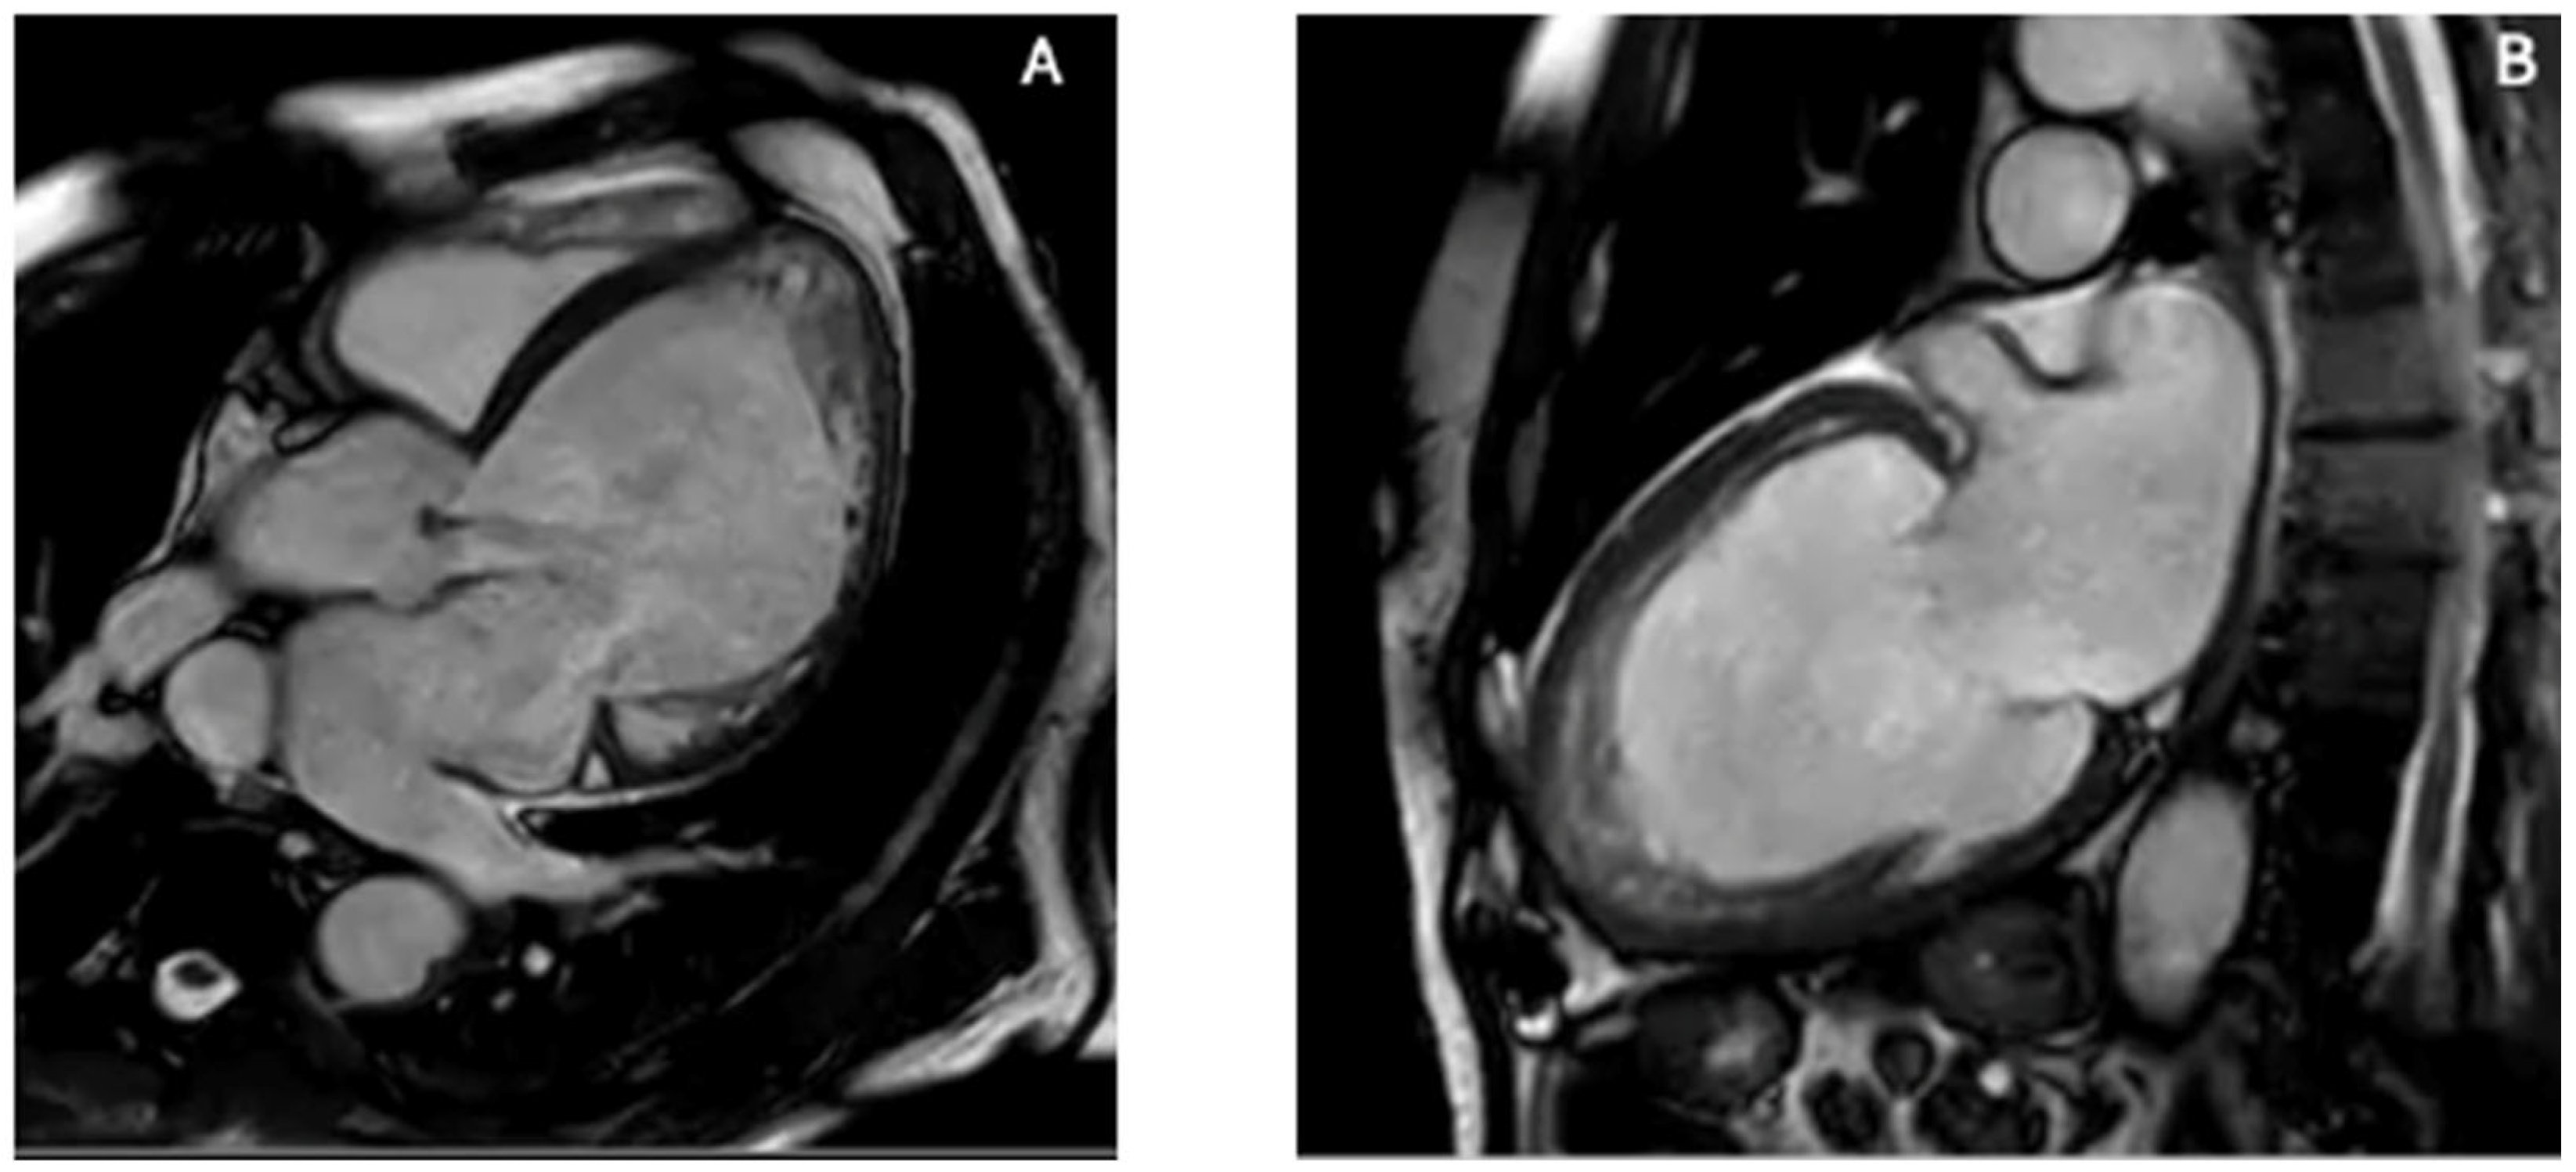

4.1. Apical Thrombosis

| Apical Thrombus | Avascular mass; improved visibility with contrast | Markedly reduced or absent apical strain | No LGE; very low T1/T2; distinct borders | CT helps assess calcified thrombi |